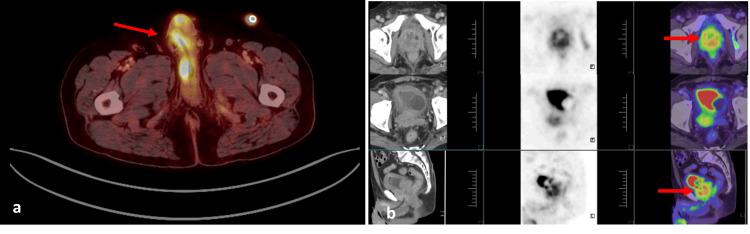

Malignant priapism is a rare and serious manifestation that results from advanced malignancy. It is caused by the infiltration of tumour cells into the penile tissue. Genitourinary cancers are the most common cause, especially prostatic adenocarcinoma. It indicates widespread metastatic disease and is associated with a poorer prognosis. It presents as a prolonged, painful erection that is not related to sexual activity and is often refractory to conventional treatments. It is rare and usually diagnosed late in the disease course. We report a 70-year-old male who underwent transurethral resection of the prostate (TURP) and bilateral orchidectomy for locally advanced prostatic adenocarcinoma and lost to follow-up. He presented six months later with painful priapism, multiple penile nodules, and acute urinary retention. Imaging studies, including high-resolution penile ultrasound and 18F-fluorodeoxyglucose positron emission tomography (18F-FDG PET) scan, confirmed multiple penile metastatic deposits. Despite initial pain management with nonsteroidal anti-inflammatory drugs (NSAIDs) and opioids, his refractory symptoms necessitated a total penectomy with perineal urethrostomy. Histopathological examination confirmed infiltrating carcinomatous deposits. Unfortunately, despite aggressive management, the patient eventually succumbed to the disease. This report emphasizes the aggressive character of penile metastases from prostate cancer, the challenges in diagnosis and treatment, and the need for a multidisciplinary approach. Early recognition and palliative strategies are essential for maximizing the quality of life.

恶性阴茎异常勃起是一种由晚期恶性肿瘤导致的罕见且严重的表现。它是由肿瘤细胞浸润阴茎组织引起的。泌尿生殖系统癌症是最常见的病因,尤其是前列腺腺癌。它表明存在广泛的转移性疾病,且预后较差。其表现为与性活动无关的持续性、疼痛性勃起,通常对传统治疗无效。它很罕见,且通常在病程晚期才被诊断出来。我们报告一例70岁男性,因局部晚期前列腺腺癌接受了经尿道前列腺切除术(TURP)和双侧睾丸切除术,之后失访。6个月后,他出现疼痛性阴茎异常勃起、多个阴茎结节及急性尿潴留。包括高分辨率阴茎超声和18F-氟脱氧葡萄糖正电子发射断层扫描(18F-FDG PET)在内的影像学检查证实阴茎有多处转移灶。尽管最初使用非甾体类抗炎药(NSAIDs)和阿片类药物进行了疼痛管理,但他的顽固性症状仍需要行全阴茎切除术与会阴尿道造口术。组织病理学检查证实有浸润性癌灶。不幸的是,尽管进行了积极治疗,患者最终仍死于该病。本报告强调了前列腺癌阴茎转移的侵袭性、诊断和治疗中的挑战以及多学科方法的必要性。早期识别和姑息治疗策略对于提高生活质量至关重要。